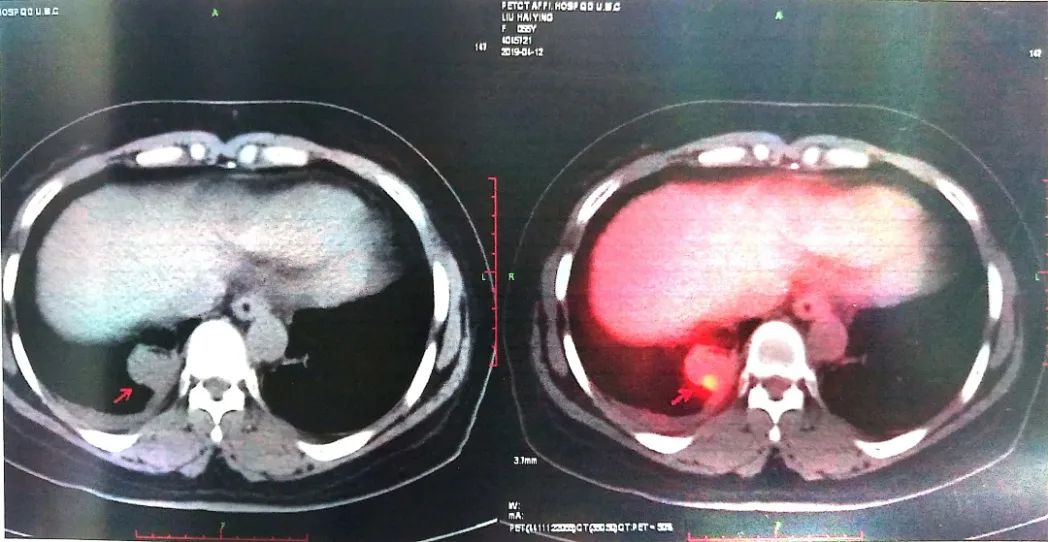

2019-04-12 PET-CT显示①右肺下叶后基底段胸膜下软组织密度肿块(大小26*30mm)。

②左肺下叶纵隔旁软组织密度肿块(大小28*31mm)。

③双肺门、纵隔内隆突下、气管旁、主肺动脉窗、血管前间隙、右侧颈部Ⅴ区及锁骨区多发增大淋巴结。